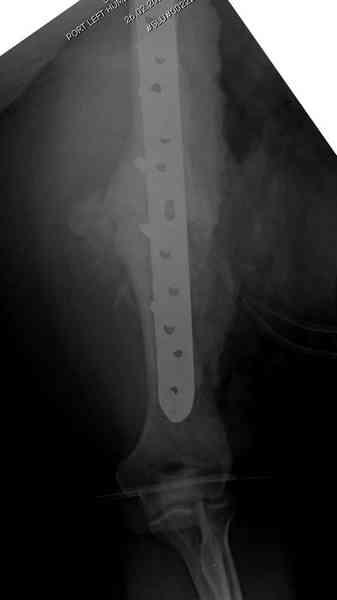

Помогите, пожалуйста, определиться с тактикой!Поступил больной с ложным суставом плечевой кости... Перелом был 2 года назад. Лечился в аппарате 8 месяцев, консолидации не произошло. В феврале 2007 выполнена костная аутопластика, фиксация пластиной (на базе одной из ИК). Сейчас сохраняется ложный сустав, плечо укорочено на 3 см, контрактура обоих смежных суставов, атрофия мышц плеча и плечевого пояса справа. Явлений остеомиелита не отмечалось. Больной - осужденный, сидеть ему до 2012 года.

Как видно из выступлений коллег, способы фиксации

ложного сустава плеча могут быть различными, кто-то предпочитает аппаратом Илизарова (Соломин), пластинами (Волна) или интрамедуллярным гвоздем (Челноков).